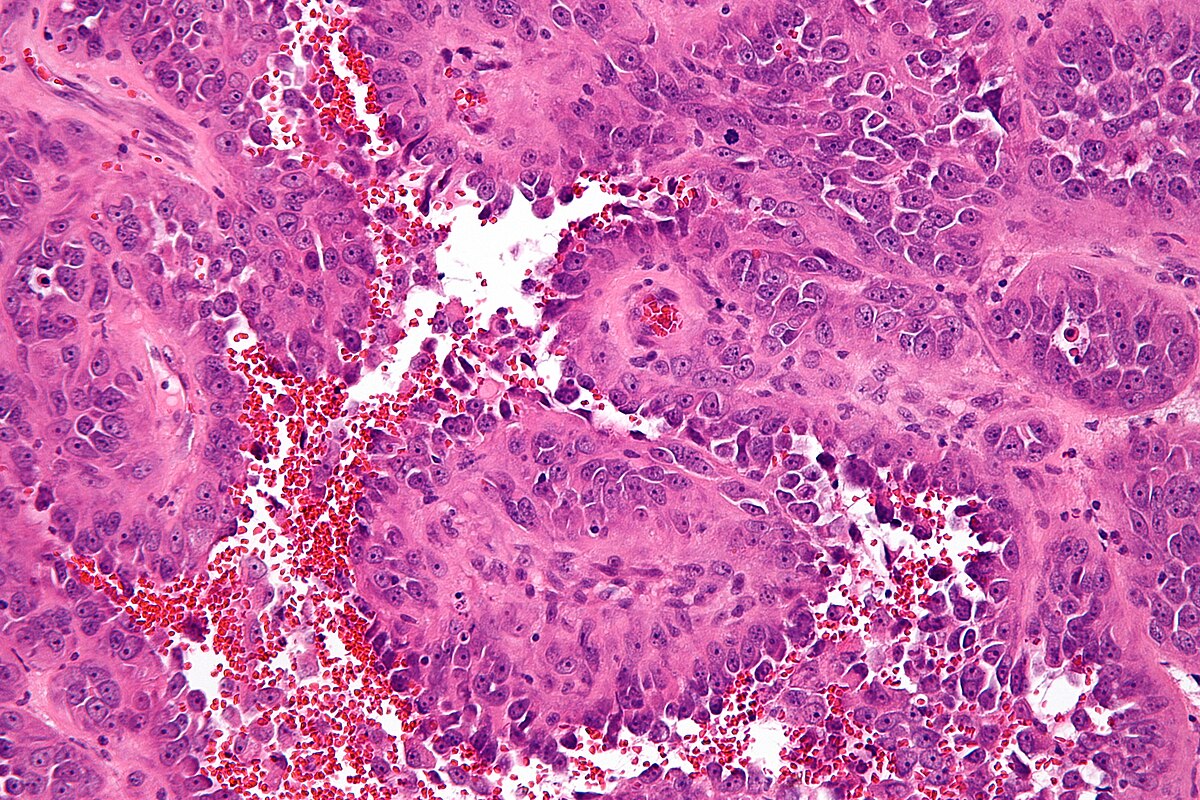

L’angiosarcome est un sarcome des tissus mous qui prend naissance dans les cellules qui tapissent les vaisseaux sanguins ou lymphatiques. La variante épithélioïde se distingue par son aspect microscopique : les cellules cancéreuses prennent une forme similaire à celle du tissu épithélial, ce qui complique souvent le diagnostic.

L’angiosarcome épithélioïde peut imiter de nombreuses maladies cutanées ou inflammatoires. Les symptômes n’étant pas très spécifiques, le diagnostic est souvent tardif.

Seule une biopsie réalisée par un spécialiste peut apporter une confirmation fiable.